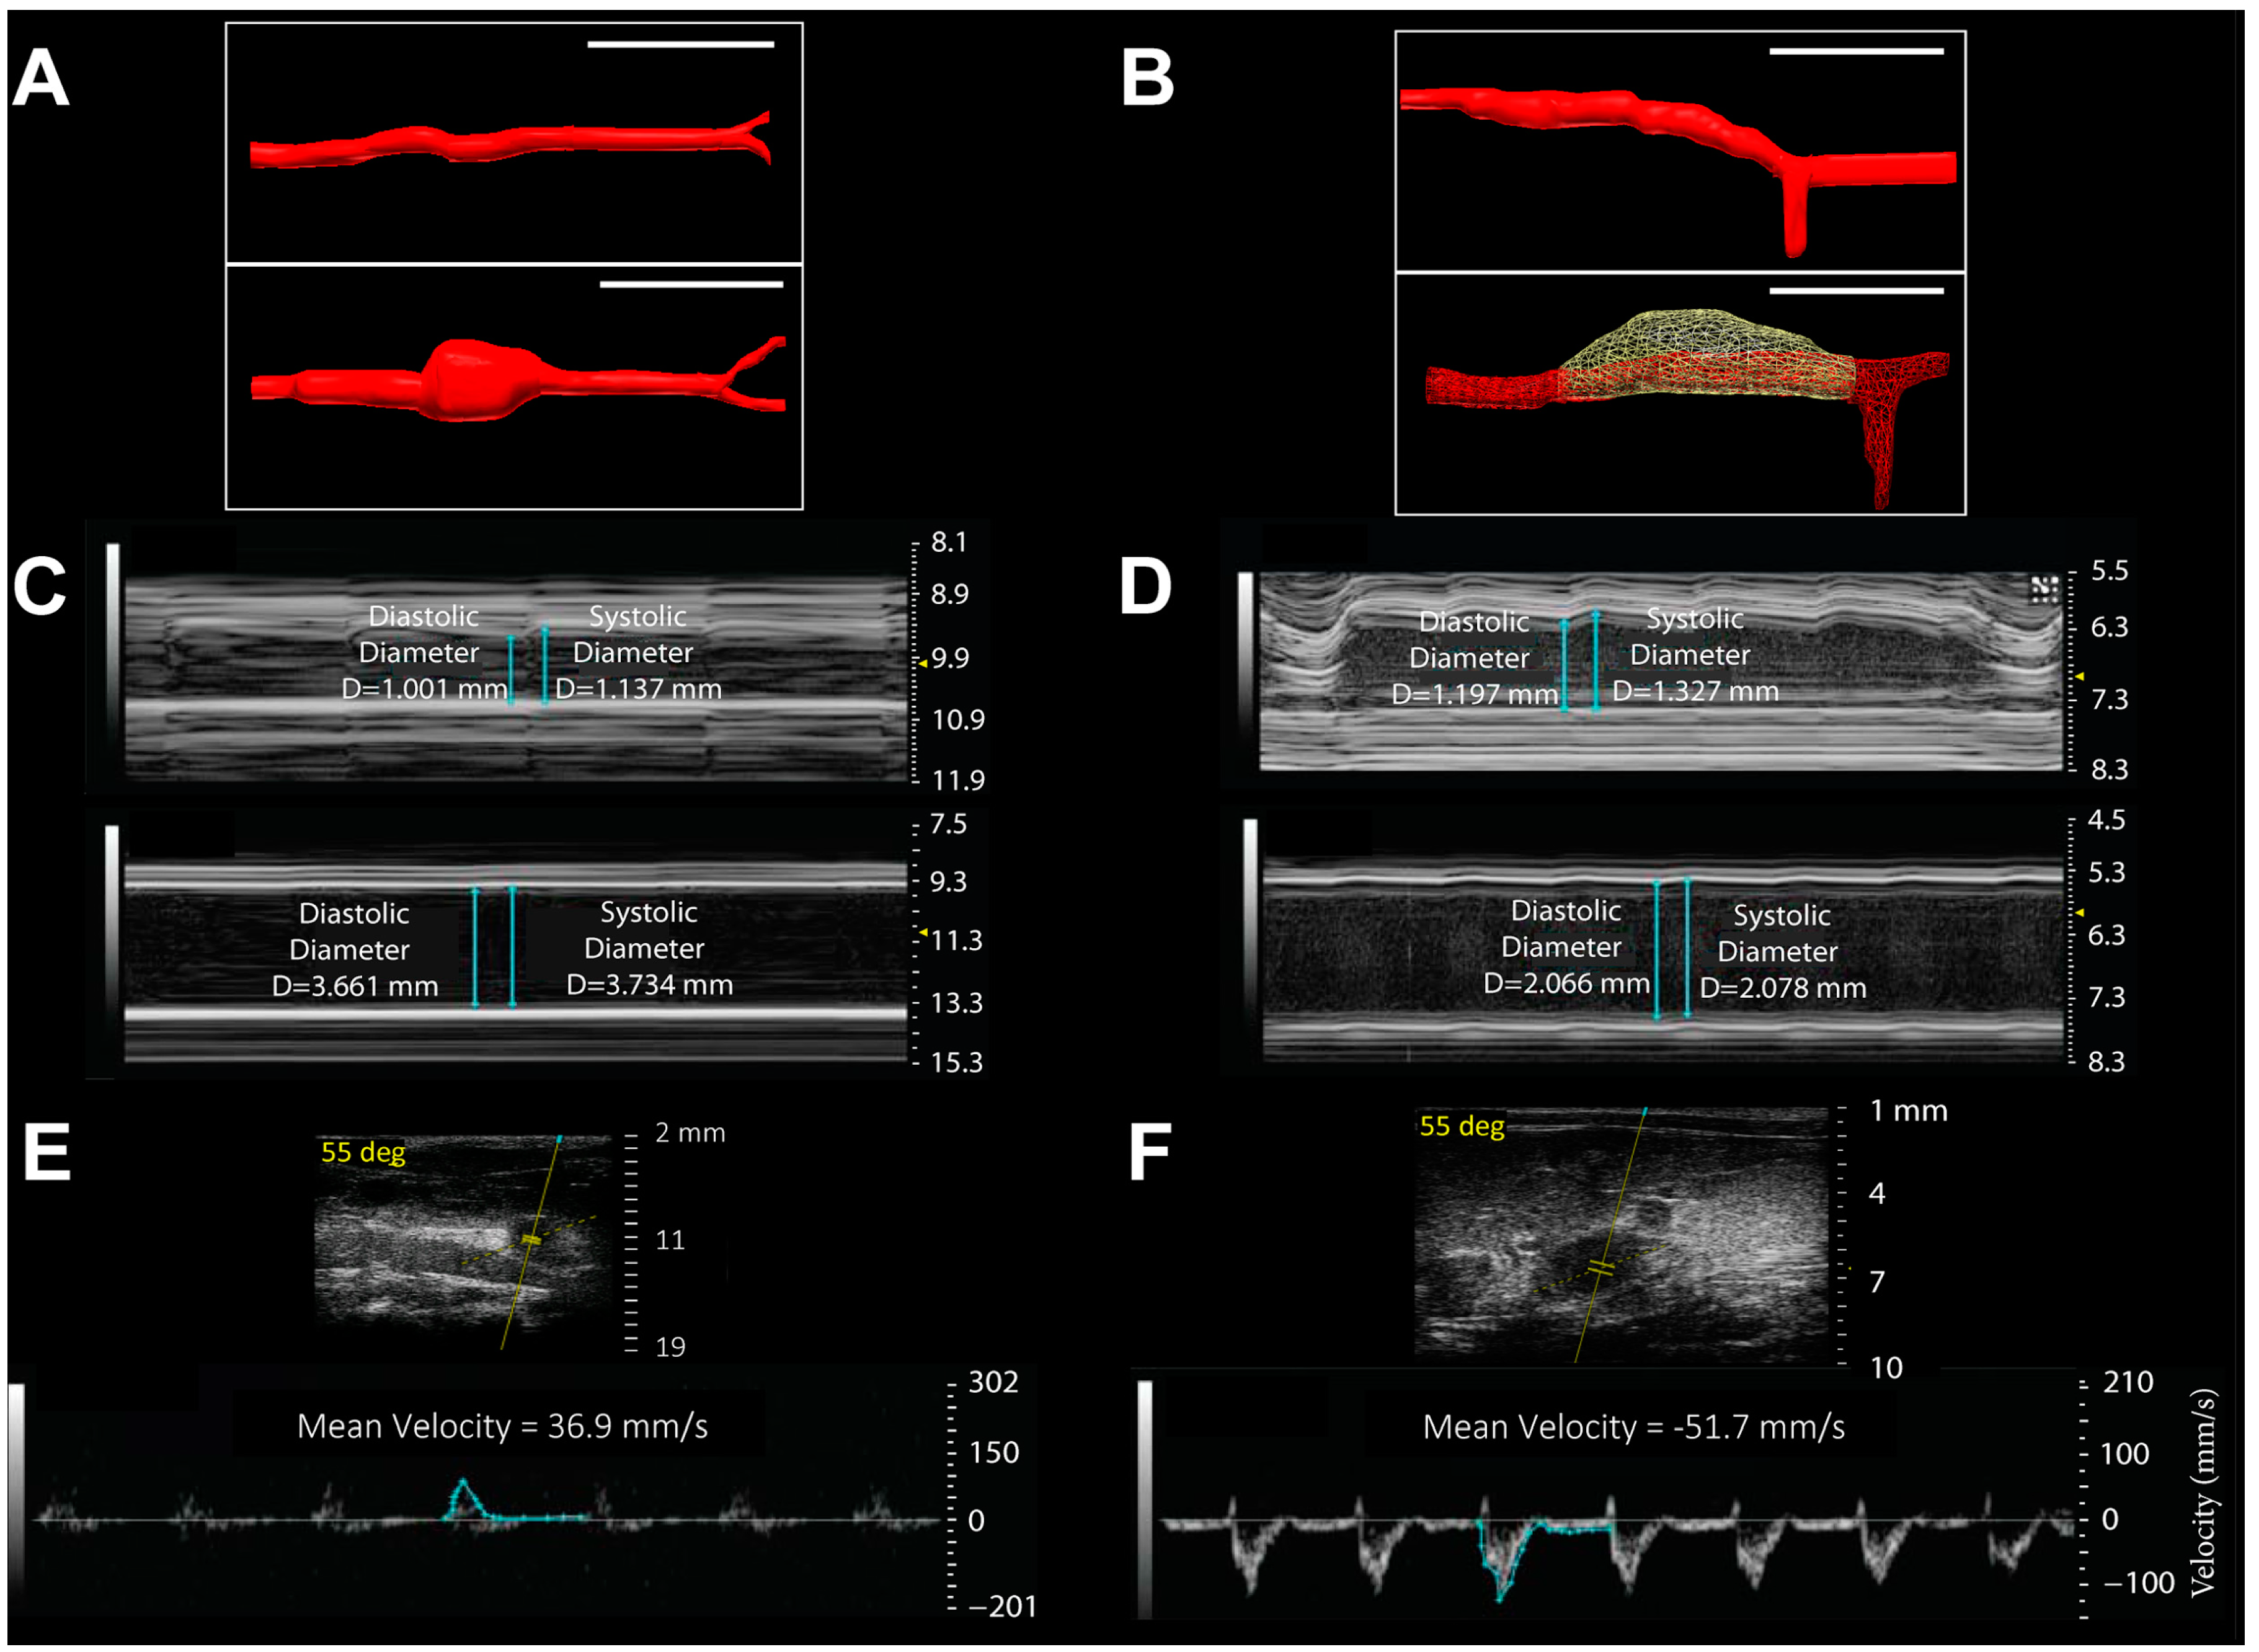

- Phillips, E.H.; Yrineo, A.A.; Schroeder, H.D.; Wilson, K.E.; Cheng, J.-X.; Goergen, C.J. Morphological and biomechanical differences in the elastase and AngII apoE−/− rodent models of abdominal aortic aneurysms. BioMed. Res. Int. 2015, in press. [Google Scholar]